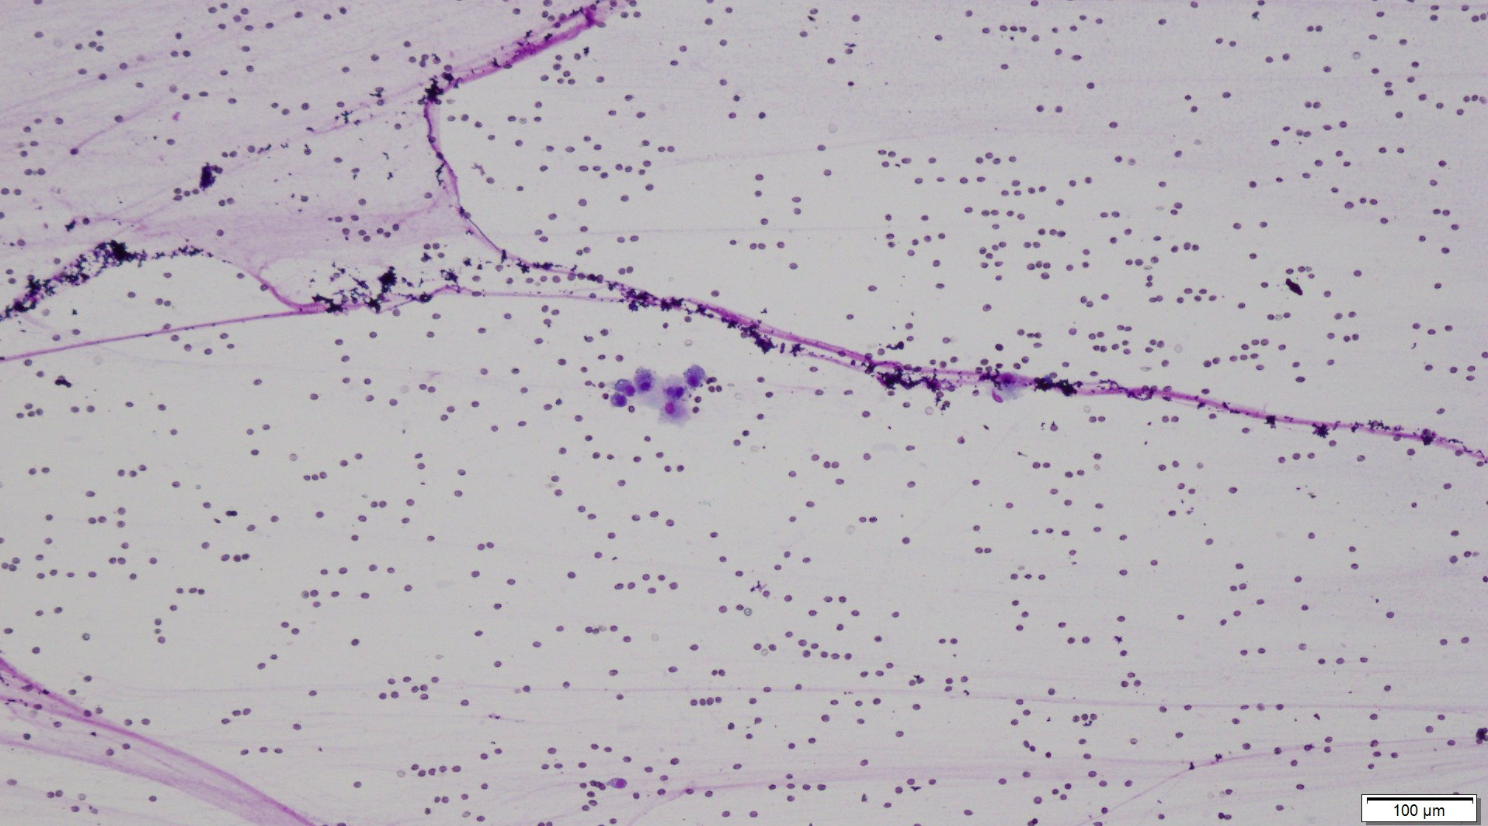

Synovial fluid analysis:

Parameter Result Ref. Range

Color of fluid Red Clear to straw-colored

Turbidity Marked None

Viscosity Marked Marked

Total nucleated cell count 2,678 cells/uL <3,000 cells/uL

Total protein 2.7 g/dL <2.5 g/dL